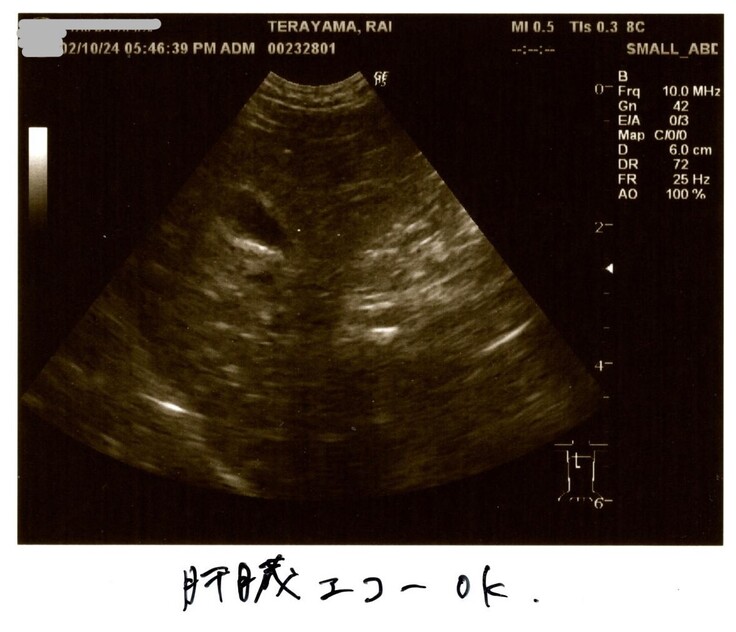

2/10検査結果

2/10はらいくんの2度目の検査結果を聞きました。

改善傾向にある項目も多く、とても10日前に命が危なかったとは

思えない状況でした。

本当に奇跡のように感じた10日間です✨

何と検査結果は全て改善していました!

血液検査も貧血や黄疸は改善!

油断はもちろんできないけれど、基準値に近づいているものもあり✨

炎症マーカー(血液検査の炎症反応)

改善はしてきていますが、まだまだ高いのでらいくんは辛かったのだと思います。